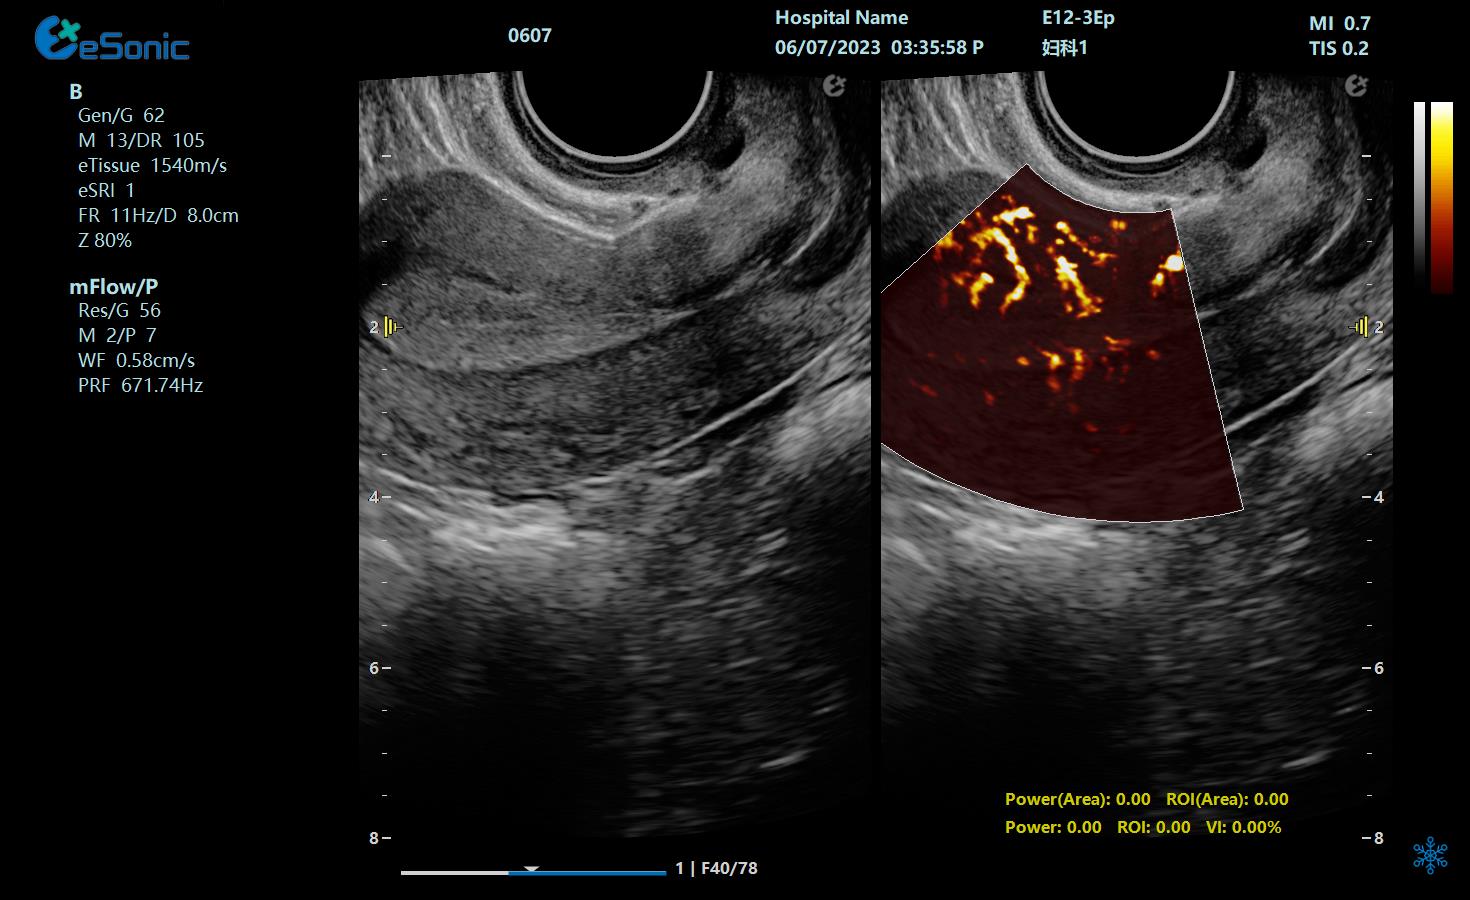

mFlow子宫内膜下螺旋动脉

mFlow微血流显像技术,细节分辨率达100μm,支持频谱多普勒及VI血管指数定量。